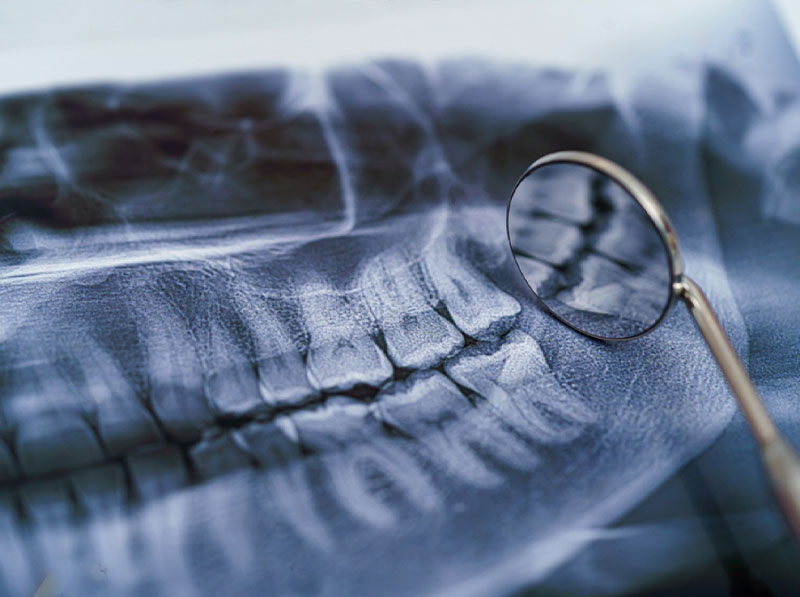

Bone grafting is a commonly used dental procedure in patients who want dental implants or other restorative treatments, but their current health does not allow for it. For a dental implant placement to be successful, the patient must have adequate jaw bone, height, and width. In most cases, when the jaw bone has deteriorated, it will not provide sufficient support for the implant or other restoration. Fortunately, advances in the oral surgery field have made bone grafting procedures much simpler, leading to reduced recovery times and improved patient outcomes.

During your consultation with Dr. Steven Haywood, an extensive evaluation of your oral health will be performed, and 3D C.B.C.T. scans of your mouth and face will likely be taken. He will also educate you about the anesthesia or sedation options to be considered for your treatment to maximize comfort. He performs several different bone grafting procedures to meet his patients’ needs.